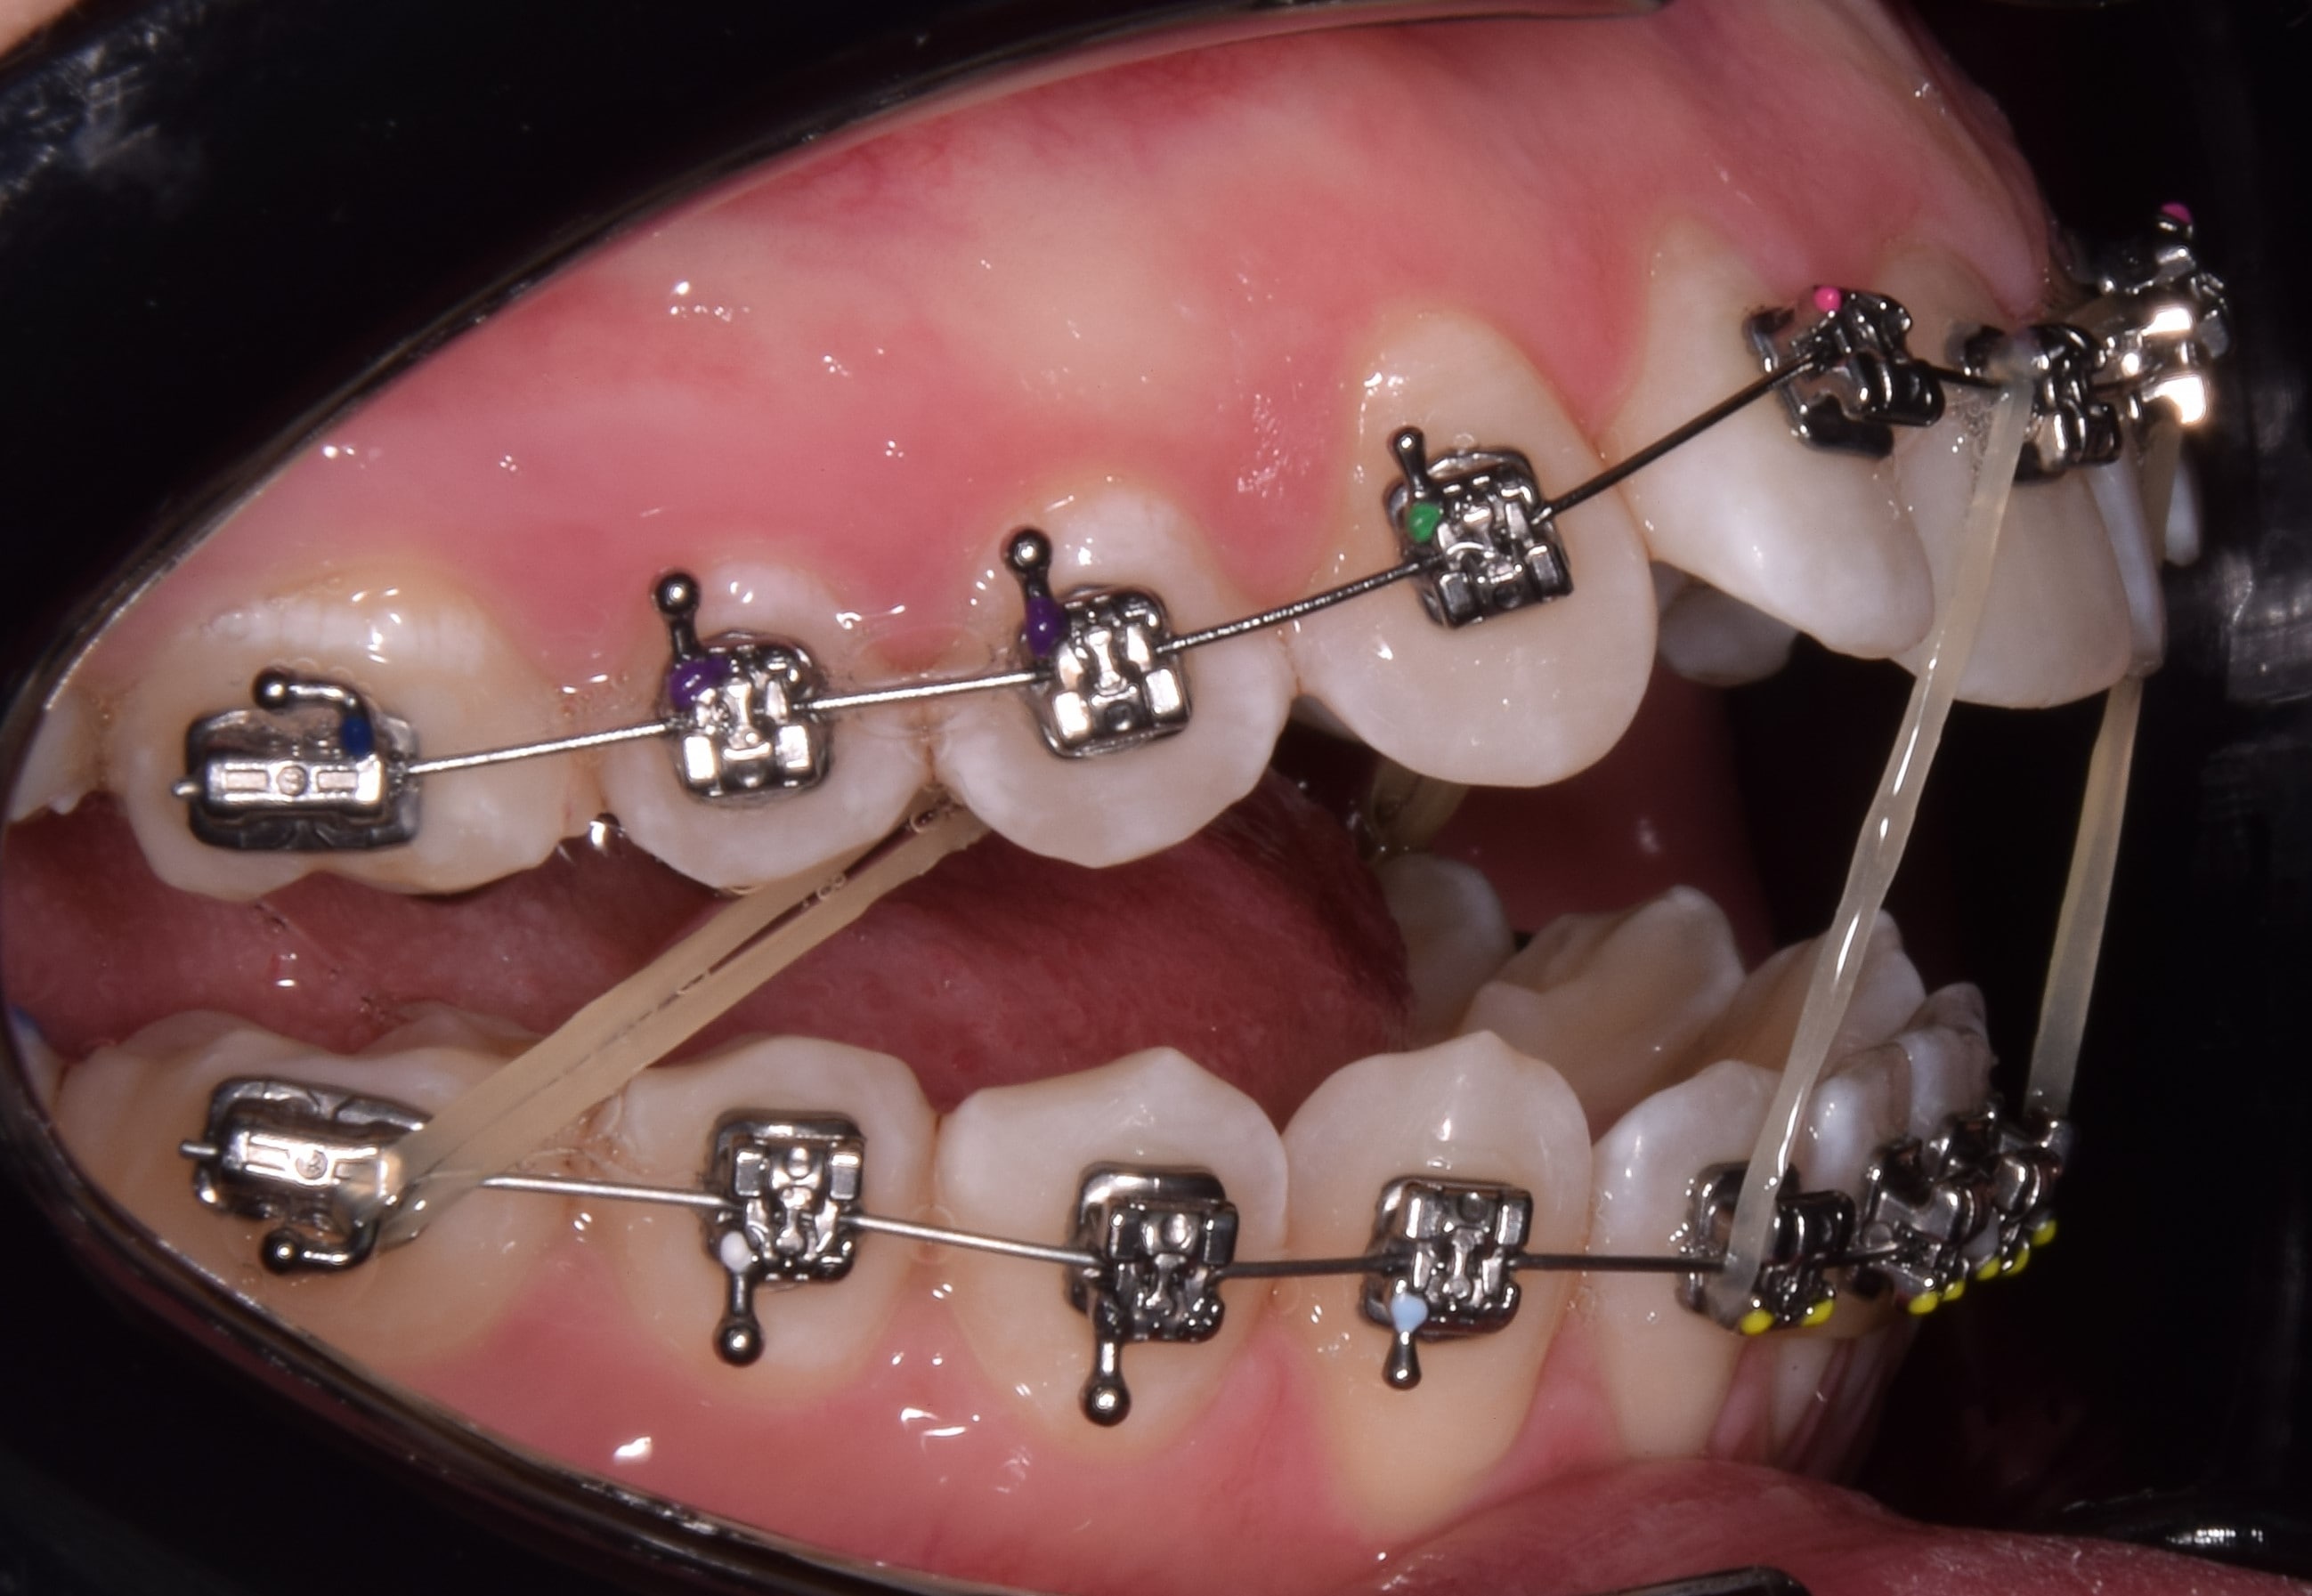

Intermaxilláris gumihúzás

A kezelések során végig elasztikus gumihúzást használunk. Ezek egyszerű, Ön által a bracketekre felhelyezhető gumikarikák, melyeket a nap 24 órájában (!!) hordani kell az általam előírt módon. A gumikat csak fogmosáskor és étkezéskor lehet eltávolítani. Érdemes lefekvés előtt új gumikarikát felhelyezni, hiszen a nap folyamán fáradás figyelhető meg az anyagban. FIGYELEM! A gumihúzás a kezelés sikerességének alappillére. A gumihúzások nem előírás szerinti használata a kezelési idő meghosszabbodásához vezet, valamint sokszor lehetetlenné teszi a tökéletes végeredmény kialakítását. Hordásuk a megszokási időszakban picit macerás, de alapfeltétele a gyors, tökéletes végeredmény elérésének.